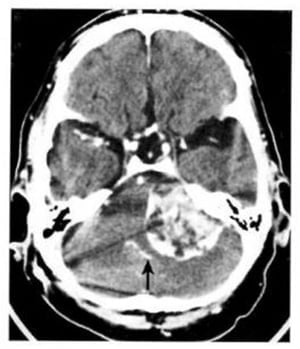

– Tổn thương mật độ cao gây chèn ép hoặc tắc nghẽn não thất 4 dẫn tới não úng thủy.

– Xuất huyết vào trong bể có thể xuất hiện như những lớp mật độ cao nằm kế cận lều tiểu não hoặc các bể.

Hình 1.68. Xuất huyết trong não thất. Não thất 4 chứa máu, giãn nở và có mật độ cao (mũi tên). Các sừng thái dương giãn nở chứng tỏ có tắc nghẽn.